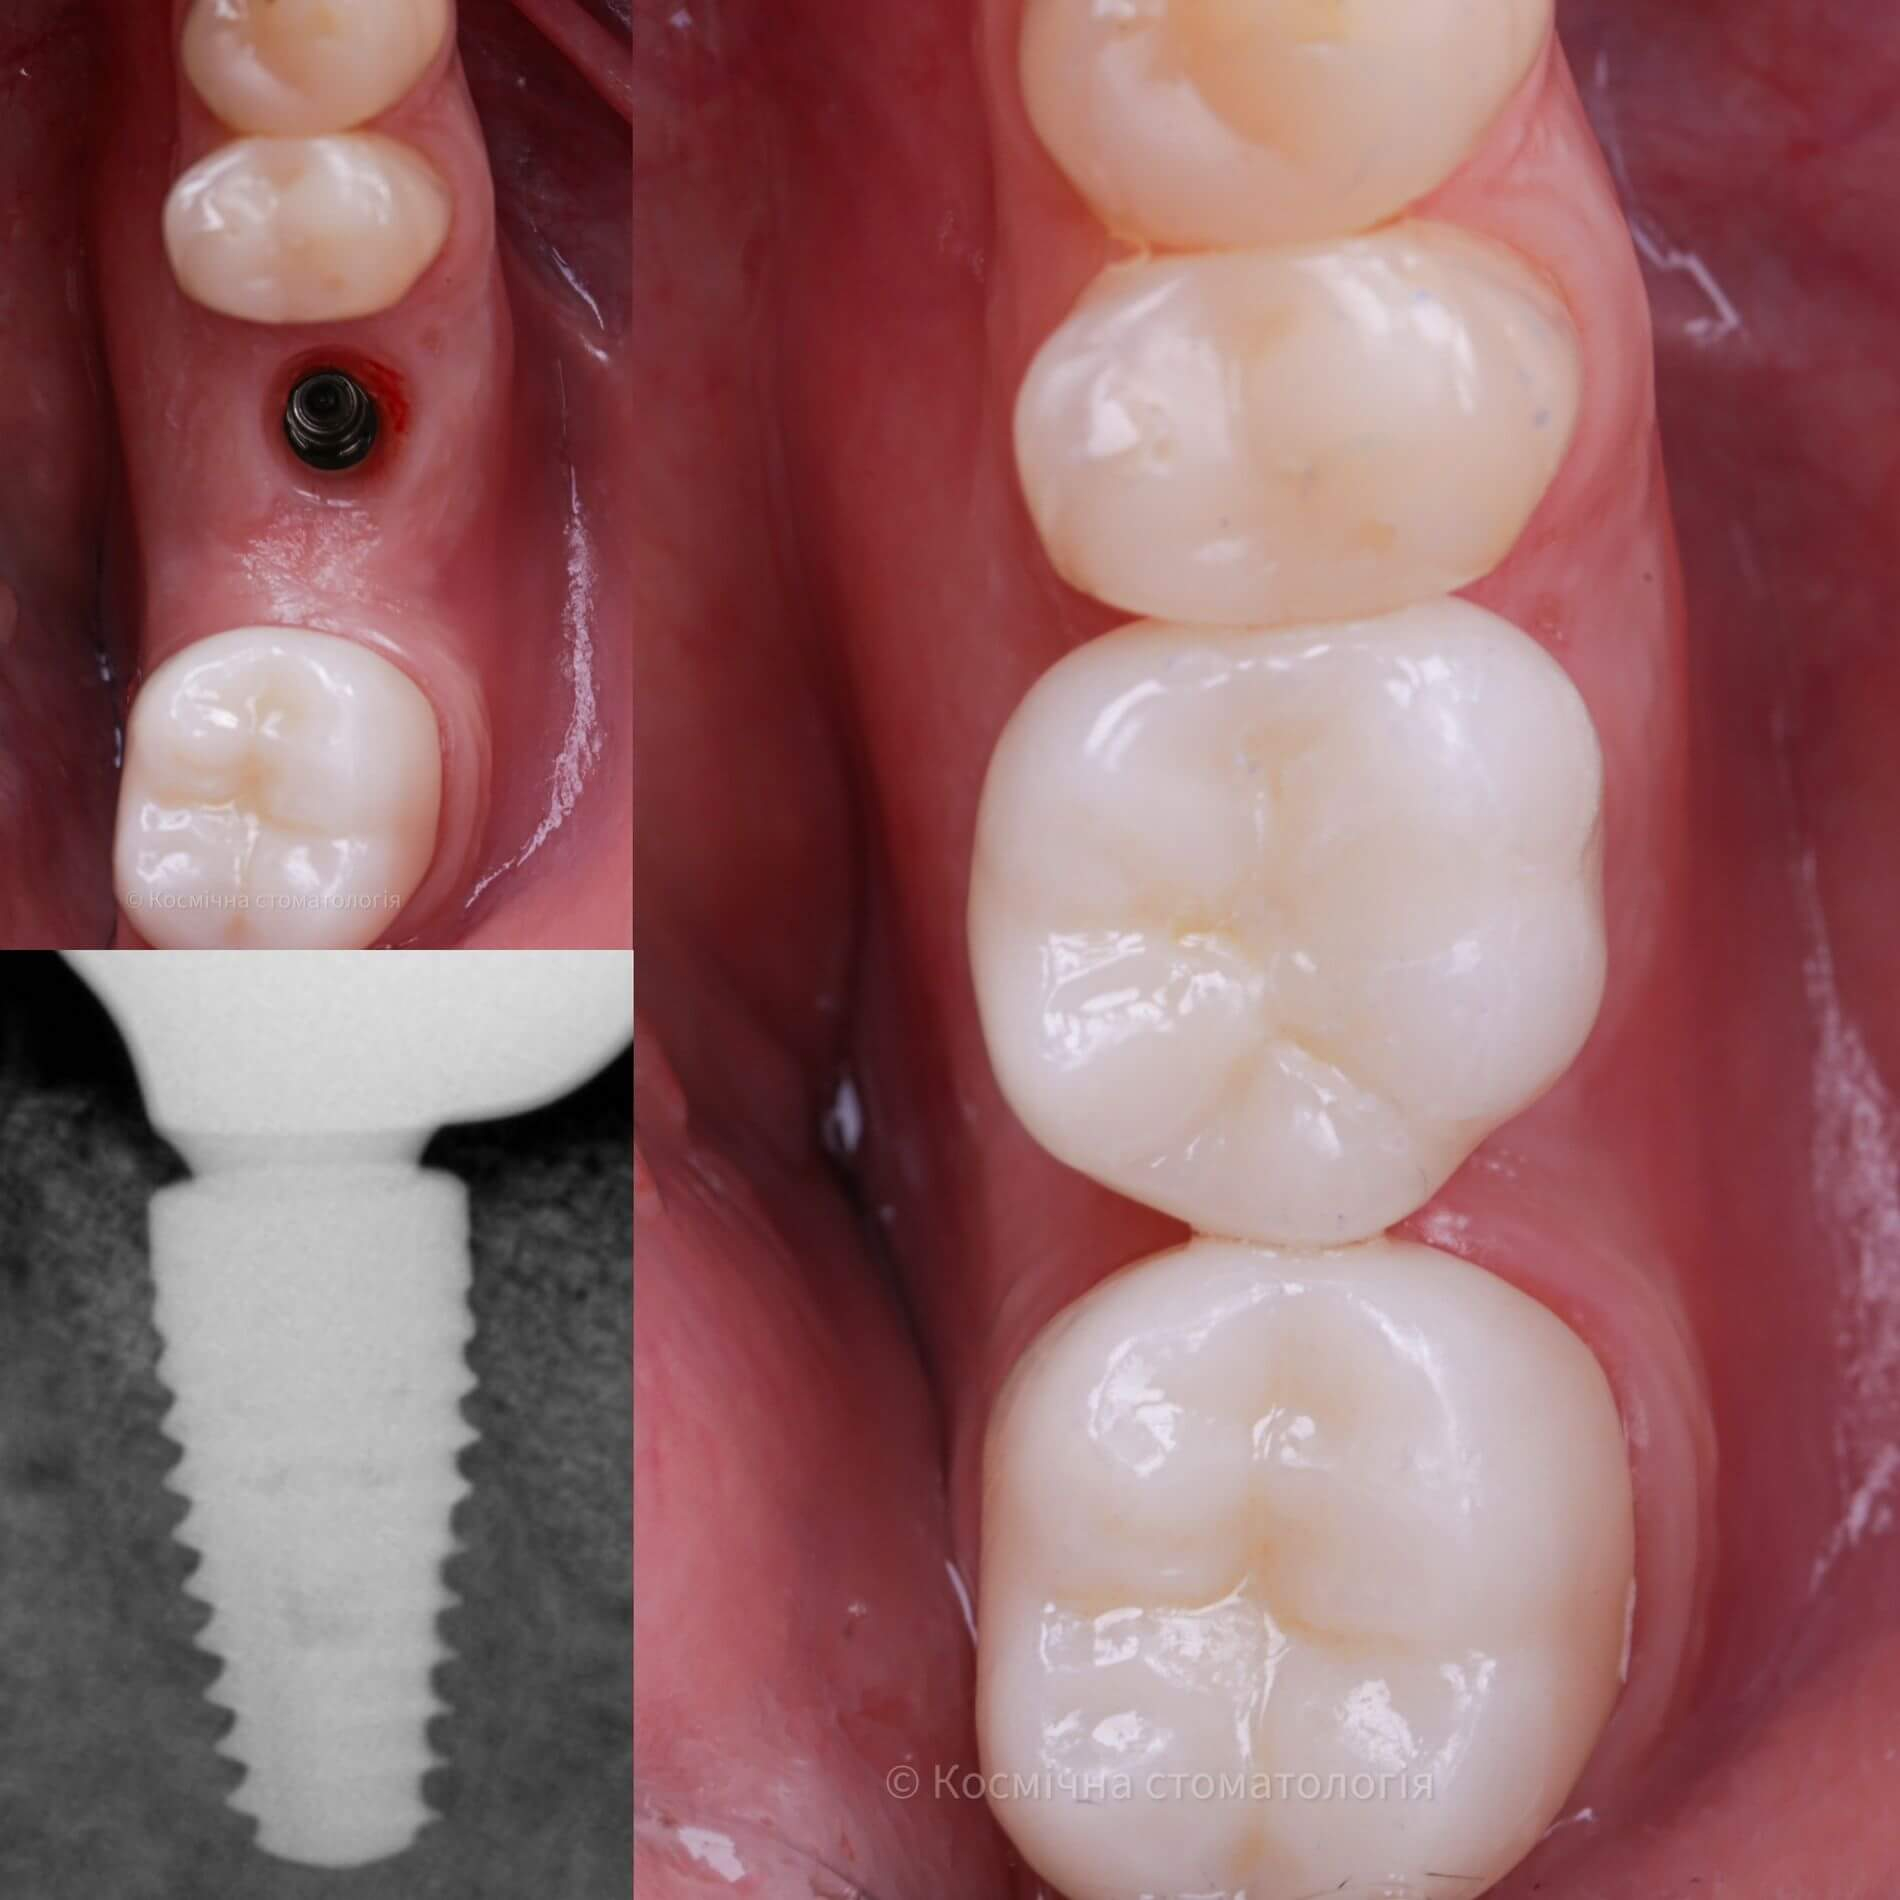

Більшість імплантів виготовляється з медичного титану. Він біосумісний, не викликає жодних реакцій та відмінно вростає в кістку щелепи.

Команда Космічної стоматології Драганчука - фанати якості та інноваційних технологій, тому обираємо імпланти кореня зуба з титану та його сплавів, зокрема Roxolid. Цей космічний сплав складається з титану та цирконію й має підвищену міцність (+30%). Це дозволяє використовувати імпланти особливо маленьких розмірів та уникнути додаткового нарощення кістки.

Команда Космічної стоматології Драганчука - фанати якості та інноваційних технологій, тому обираємо імпланти кореня зуба з титану та його сплавів, зокрема Roxolid. Цей космічний сплав складається з титану та цирконію й має підвищену міцність (+30%). Це дозволяє використовувати імпланти особливо маленьких розмірів та уникнути додаткового нарощування кістки.

Галерея